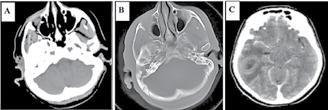

• Studiul opacifierii ramurilor corticale ale arterelor cerebrale medii (M4) drepte și stângi și a venelor cerebrale interne drepte și stângi (Fig.1).

Fig.1 ACTMS cranio-cerebrală, recon MIP în plan axial (a,b) și sagital (c): aspect normal; (a) opacifierea arterelor temporale dreaptă și stângă (săgeţi); (b) opaciferea ramurilor corticale ale arterelor cerebrale medii (M4)-săgeţi albe; opaciferea venelor cerebrale interne dreaptă și stângă (săgeţi negre-b și c).

Semiologie:

▶ Absența opacifierii M4 = 1 punct

▶ Opacifierea M4 = 0 punct

▶ Absența opacifierii venei cerebrale interne = 1 punct

▶ Opacifierea venei cerebrale interne = 0 puncte

• Un scor egal sau mai mare de 3 confirmă stopul circulator intracerebral. In acest caz, concluzia examinării este: „stop circulator intracerebral” care vine în sprijinul diagnosticului clinic de moarte cerebrală sau aspect ACT compatibil cu moartea cerebrală

• În caz contrar, concluzia examinării este „absența opririi circulatiei intracerebrale”, situaţie în care diagnosticul clinic de MC nu este confirmat.